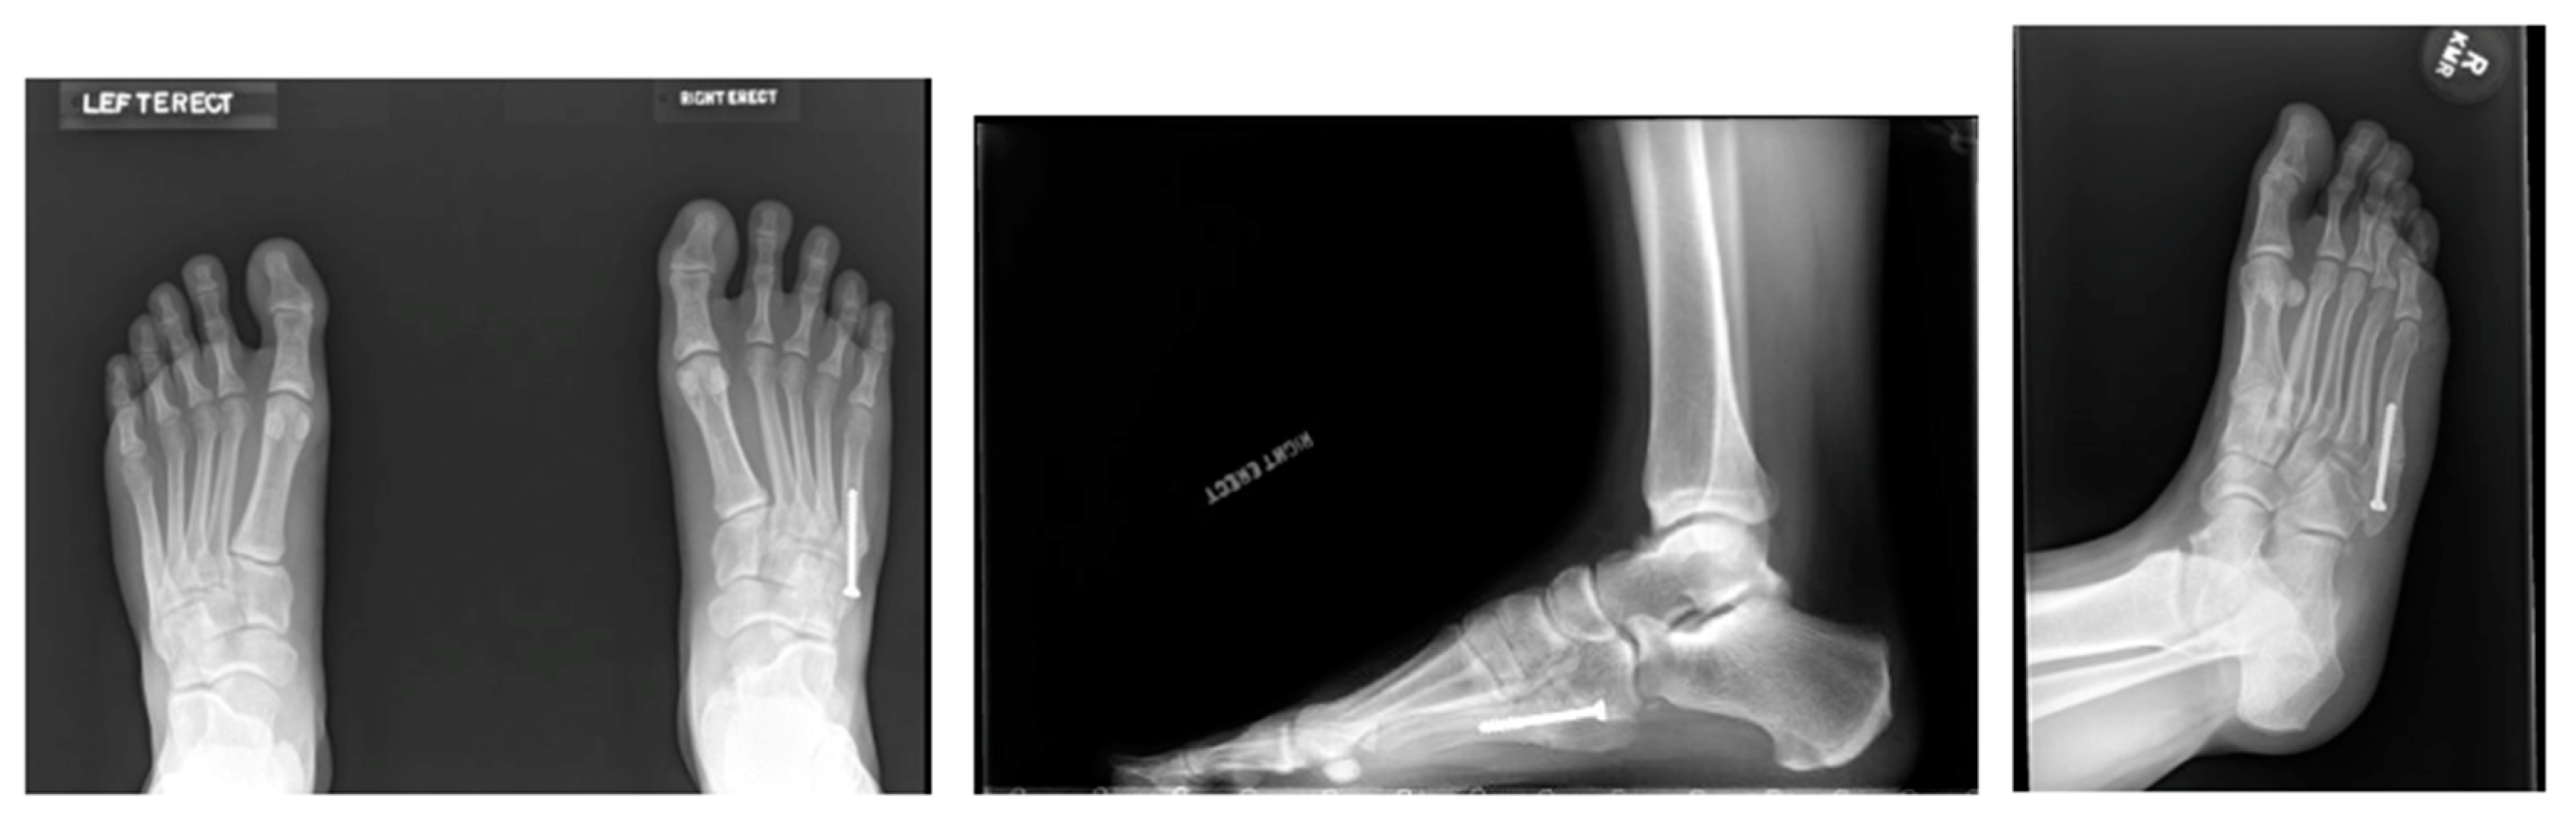

3.3.2. Surgical Treatment Techniques

- Bernstein, D.T.; Mitchell, R.J.; McCulloch, P.C.; Harris, J.D.; Varner, K.E. Treatment of Proximal Fifth Metatarsal Fractures and Refractures With Plantar Plating in Elite Athletes. Foot Ankle Int. 2018, 39, 1410–1415. [Google Scholar] [CrossRef]

- O’Malley, M.; DeSandis, B.; Allen, A.; Levitsky, M.; O’Malley, Q.; Williams, R. Operative Treatment of Fifth Metatarsal Jones Fractures (Zones II and III) in the NBA. Foot Ankle Int. 2016, 37, 488–500. [Google Scholar] [CrossRef] [PubMed]

- Young, K.W.; Kim, J.S.; Lee, H.S.; Jegal, H.; Park, Y.U.; Lee, K.T. Operative Results of Plantar Plating for Fifth Metatarsal Stress Fracture. Foot Ankle Int. 2020, 41, 419–427. [Google Scholar] [CrossRef] [PubMed]

- Albloushi, M.; Alshanqiti, A.; Qasem, M.; Abitbol, A.; Gregory, T. Jones type fifth metatarsal fracture fixation in athletes: A review and current concept. World J. Orthop. 2021, 12, 640–650. [Google Scholar] [CrossRef]

- Larson, C.M.; Almekinders, L.C.; Taft, T.N.; Garrett, W.E. Intramedullary screw fixation of Jones fractures. Analysis of failure. Am. J. Sports Med. 2002, 30, 55–60. [Google Scholar] [CrossRef]